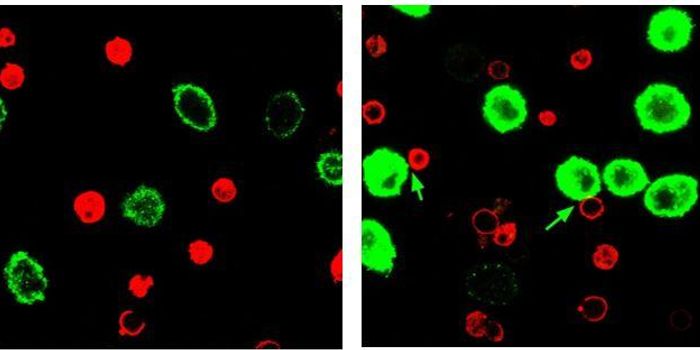

MAY 21, 2019Cell & Molecular BiologyScientists have visualized how the body tests out important defensive cells, and have captured the process on video.